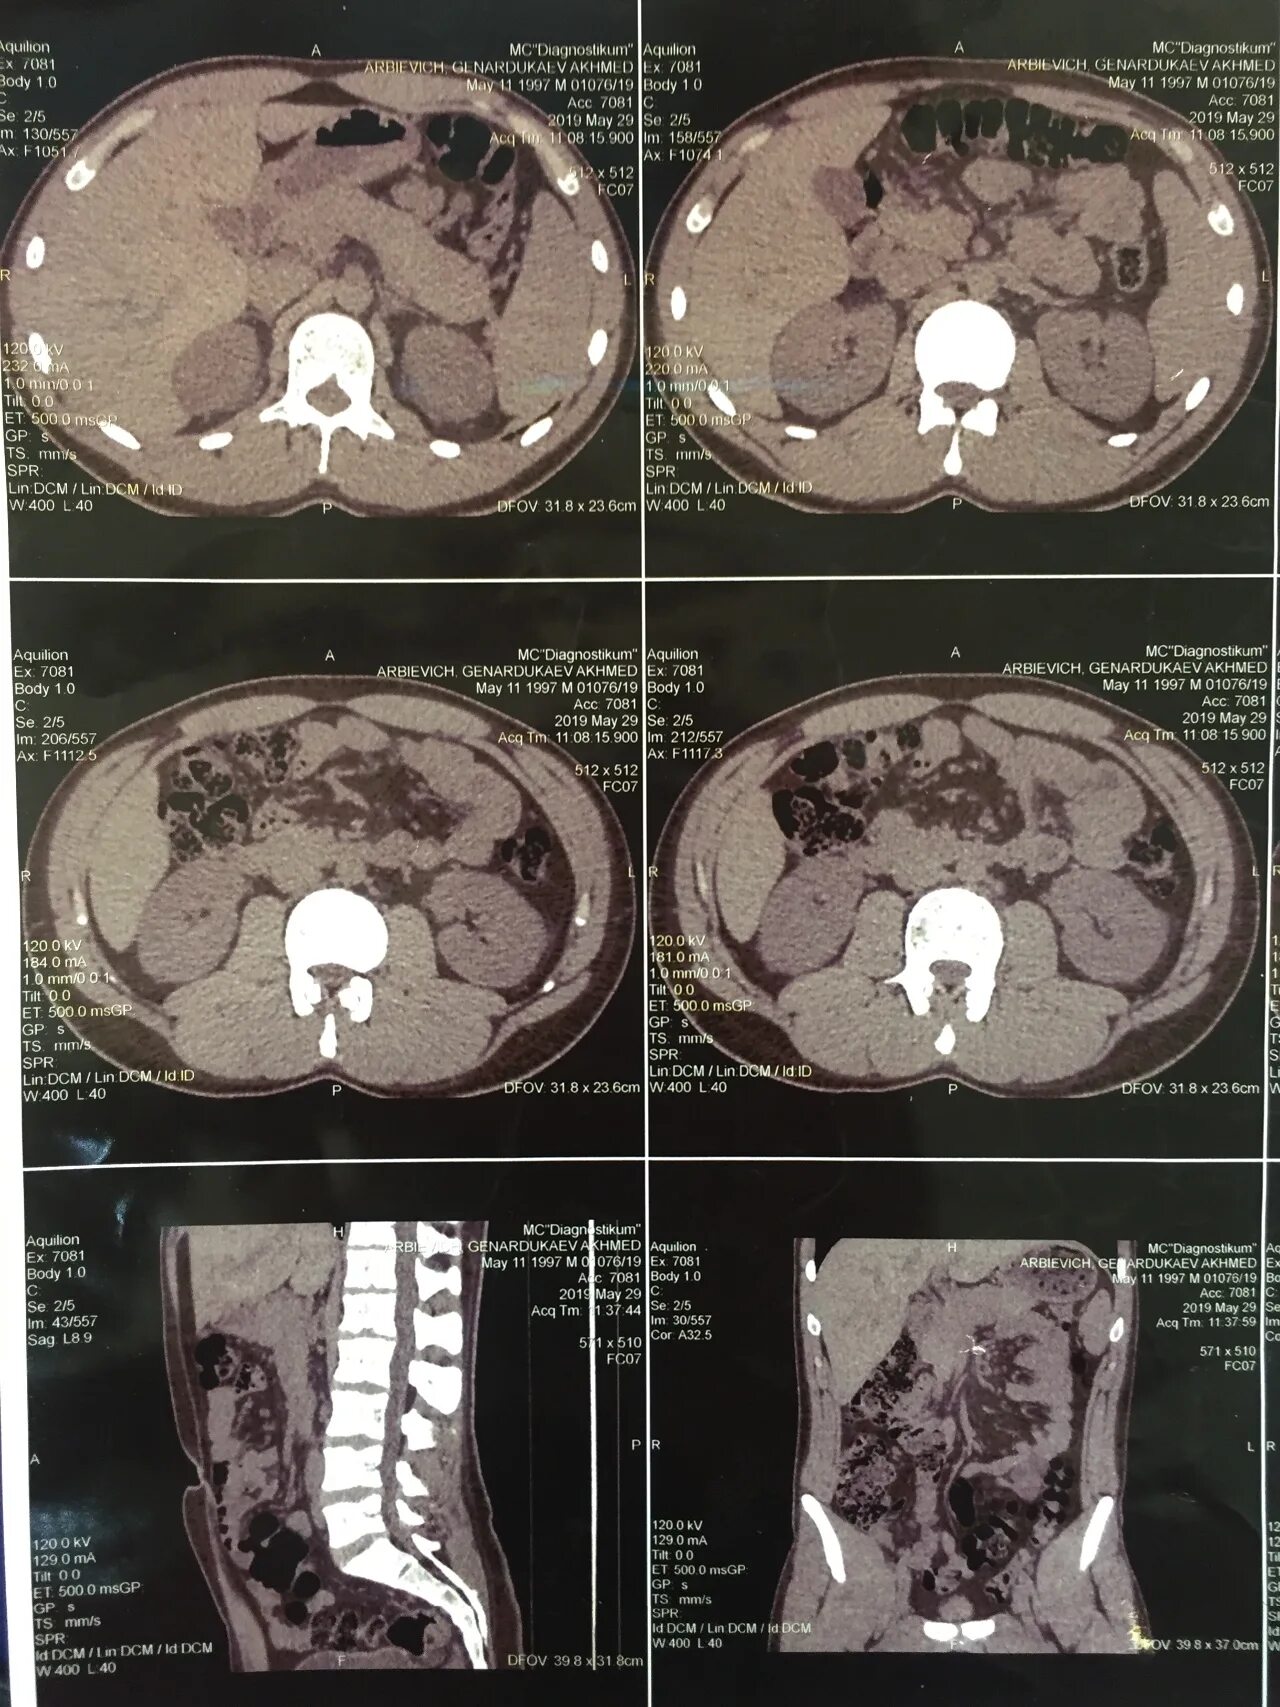

Кт брюшной полости краснодар